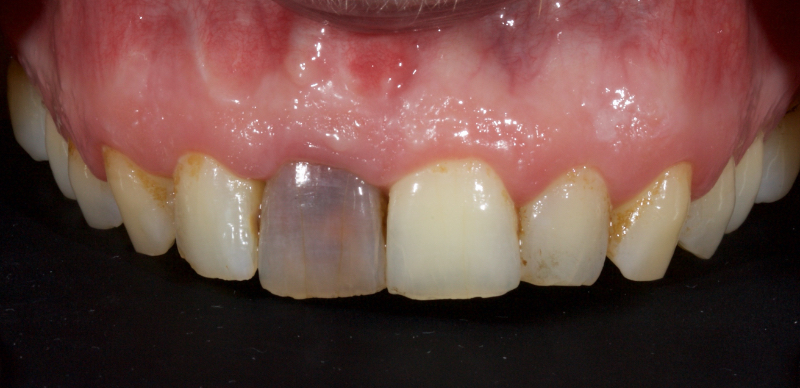

This article explores a more modern, minimally invasive approach to discolored non-vital teeth using the “modified walking bleach” approach. Figure 3 (before treatment) and Figure 4 (after treatment) show an example of this highly conservative approach.

In this example of the Modified Walking Bleach Approach, the patient presented with a discolored upper right central incisor (1.1, Fig. 7). The old restoration was removed, an endodontic retreatment was carried out, and a coronal barrier seal was placed (Fig. 8). The access cavity was left open (Fig. 9).